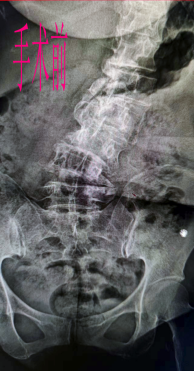

患者产某,女,52岁,潜山县王河镇人。因15年前不慎摔跌伤,髋部着地,在当地医院行X线检查提示有骨折征象,患者未予以重视,行药物保守治疗。近10年患者出现脊柱右侧侧弯现象,且情况逐渐加重,2月前病情再次加重,腰痛难以忍受,不能久站及长时间行走,脊柱活动严重受限,休息状态下腰背部即有酸胀感,遂来我院咨询骨二科主任丁士河副院长,丁院长详细询问病史并为其进行体格检查,结合相应的辅助检查结果,诊断为:继发性脊柱侧弯伴脊柱矢状位严重失衡,建议患者行手术治疗,办理住院后,丁院长随即联系安医大三附院脊柱骨科张之栋主任进行远程会诊,共同探讨并制定了手术治疗方案。7月2日在由张主任主刀、丁院长担任一助的共同努力配合下,历经5个小时成功完成了胸腰段后凸畸形截骨术、从胸10至腰6椎体的长节段侧弯矫形、钉棒内固定术,手术非常成功。高难度手术成功,不仅解决病人的痛苦,也使我科青年医师得到了一次十分难得的学习和观摩机会,获益匪浅。手术结束后患者家属对患者术后状态表示非常满意。患者术后第二天,静息状态下腰背部已无明显酸胀感,且下肢麻木酸胀感也较前明显缓解,目前正指导患者行功能康复锻炼。